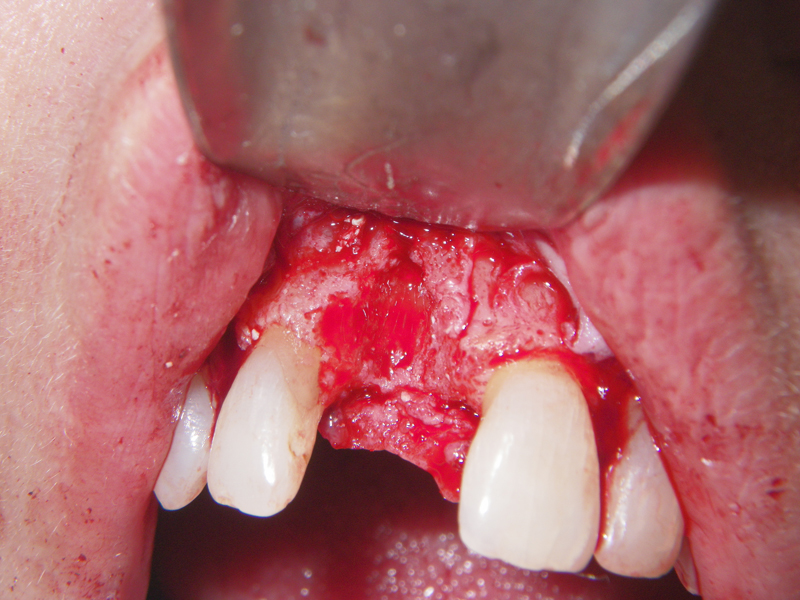

- Incision

- Identify, don’t ‘skeletonize,’ mental nerves

- Midline, lateral score marks

- Osteotomy 5 mm below tooth apices & mental nerve

- Downfracture (release ‘wings’)